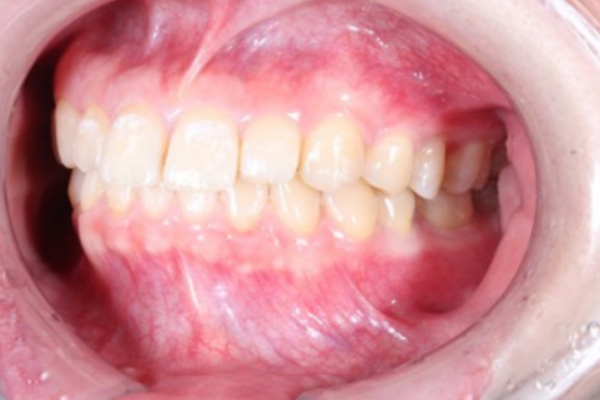

術前

術後